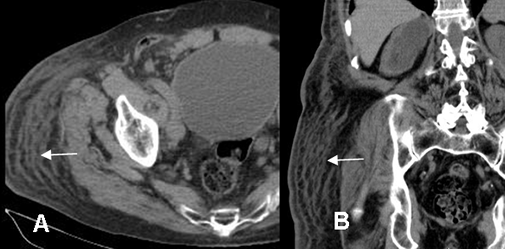

En la infección no complicada se encuentra engrosamiento de la piel, la fascia muscular, septación de la grasa subcutánea y captación variable del contraste, tanto en la TAC como la RM. (2, 12). (Fig 12 y 13).

Fig 12. Celulitis.

A: TAC axial y B: TAC coronal. Engrosamiento y trabeculación de la grasa subcutánea en la región glútea derecha, la cual capta el contraste, por celulitis.